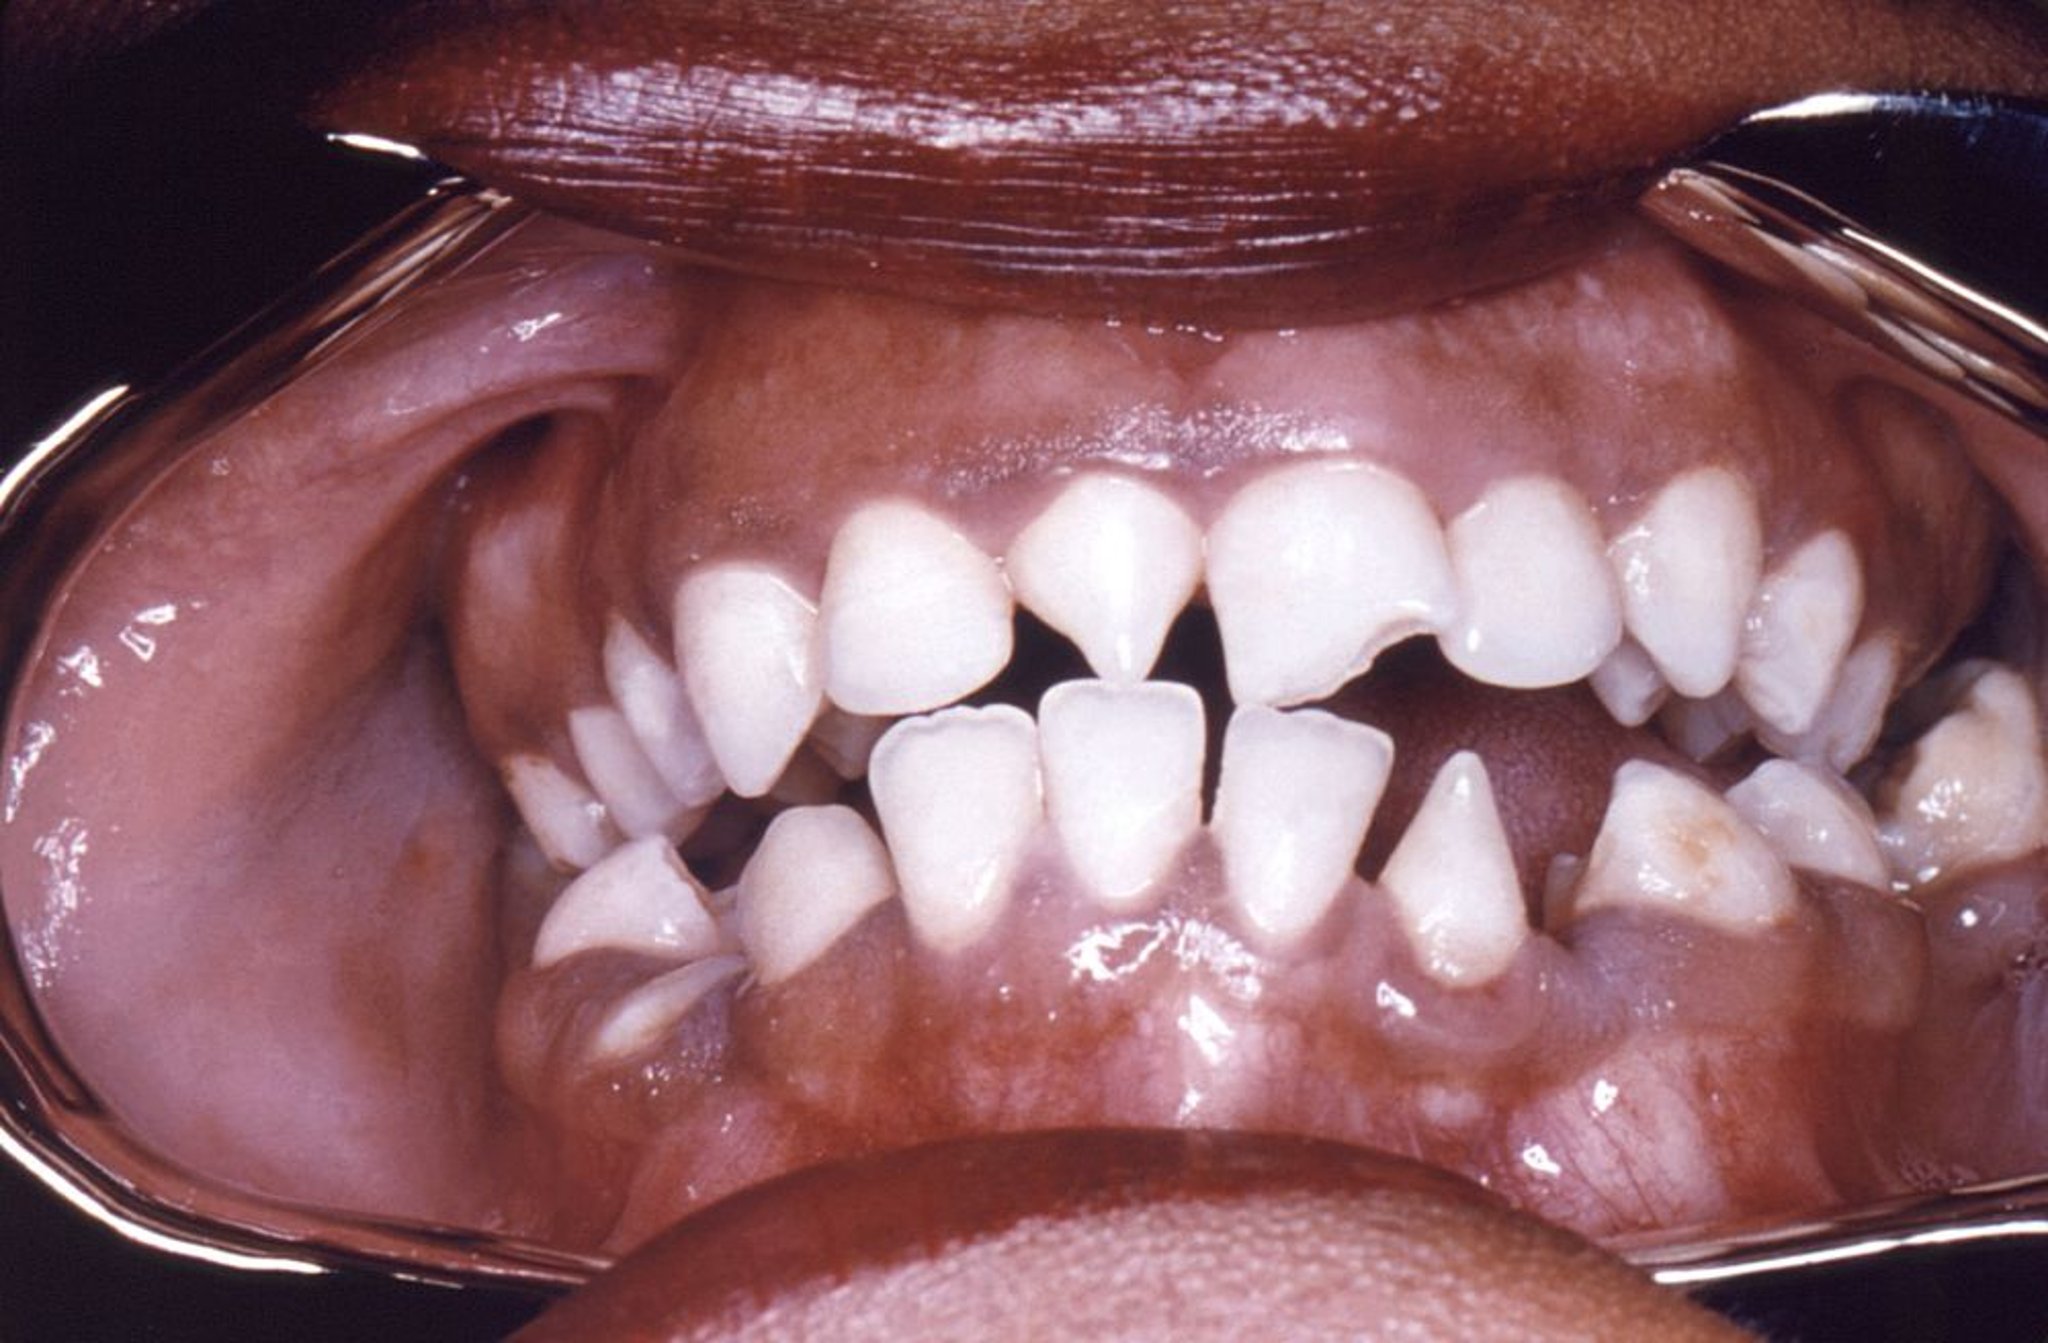

Incisives d'Hutchinson

Cette photo montre une déformation de forme triangulaire des incisives inférieures droite et gauche provoquée par la syphilis congénitale.

Image courtoisie de Robert E. Sumpter via the Public Health Image Library of the Centers for Disease Control and Prevention.